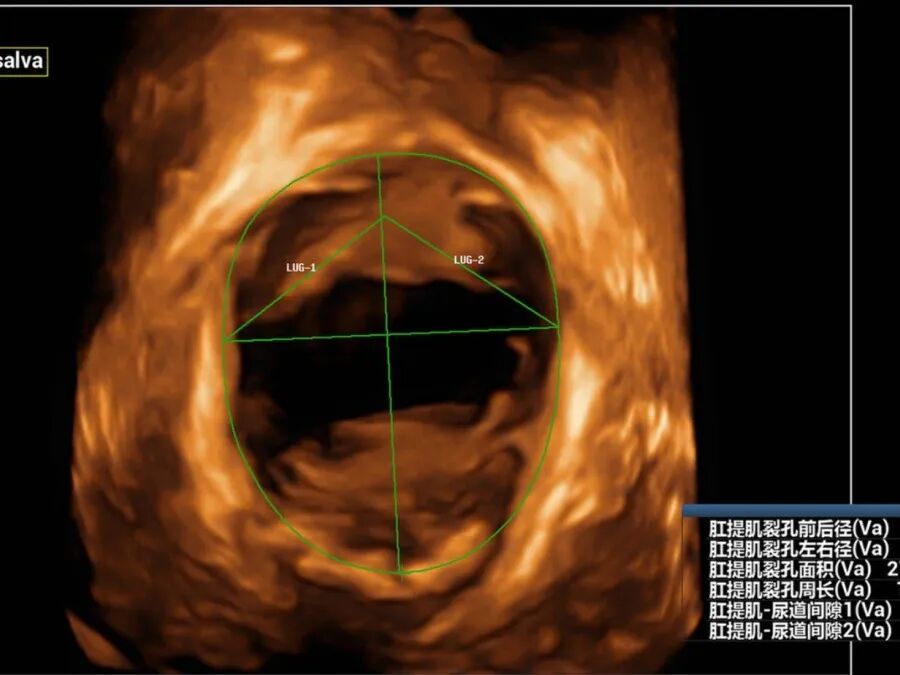

近日,54岁的黄女士因“尿失禁13年”来我院妇女保健科就诊,黄女士讲述了近十年来经常发生尿频尿急憋不住尿的经历,自己咳嗽、大笑或者长时间走路后便出现漏尿等尴尬症状,严重影响正常生活和社交活动。由于涉及隐私部位,怕人笑话,一开始她不敢跟身边的人说起这件事,能忍则忍。最近随着症状加重,难以忍受,终于来我院就诊。 在妇女保健科医师颜惠芳建议下,黄女士前往我院超声医学科行四维盆底超声检查,检查后发现黄女士有膀胱脱垂、子宫脱垂的现象,诊断为“压力性尿失禁”,终于找到漏尿的原因了,黄女士的治疗也可以针对性开展。 现实生活中,不少女性朋友也有过这样尴尬的经历,大笑、打喷嚏、咳嗽时尿液溢出外出时总想找厕所,私密处总有异物感,腰酸背痛,下腹坠胀,夫妻生活不和谐……种种难言之隐羞于说出口,却又如影随形。这一切的罪魁祸首很可能是——盆底功能障碍。 一、什么是盆底功能障碍 盆底功能障碍是指盆底肌肉、筋膜、韧带等支持结构受损而导致的一系列临床症候群,如压力性尿失禁、子宫等盆腔脏器脱垂、粪失禁、梗阻型便秘和性功能障碍等。妊娠和分娩是造成此病的首要原因,其中以经阴道分娩危险性最高,当前已成为影响全球妇女身心健康的五种最常见疾病之一,被称为“社交癌”。 二、为什么会发生盆底功能障碍? 怀孕、分娩、衰老、肥胖、长期便秘、慢性咳嗽、长期提重物等原因,都会导致盆底肌损伤,分娩是造成盆底肌损伤的主要原因。 通常胎儿头部大小都会大于正常的阴道大小,分娩时,阴道会受到胎儿头部的挤压而扩张,造成盆底肌肉损伤。双胎、巨大儿、分娩两次及以上的妈妈们,盆底肌受到的损伤通常会加倍。产后和围绝经期为高发期,被称为严重影响女性生活质量的五大慢性病之一。 三、什么是盆底超声? 盆底超声是使用特殊配置的超声仪器,利用二维图像、三维重建、动态四维显示联合应用,在患者静息、缩肛、valsalva不同状态下,直观了解盆底的静态、动态结构、显示耻骨联合、尿道、膀胱、阴道、宫颈、直肠壶腹及肛管等结构,从而评估盆底各脏器位置、功能,脏器脱垂情况、盆底肌有无损伤等。 盆底超声适应症: 1.盆腔脏器脱垂:膀胱脱垂、子宫脱垂、直肠膨出等; 2.排尿异常:压力性尿失禁、尿潴留、排尿困难等; 3.排便异常:粪失禁、便秘等; 4.性功能障碍:性交痛、性欲降低等; 5.慢性盆腔痛:下腹部疼痛、腰骶部或会阴痛等; 6.产后女性(42天至6个月)盆底功能障碍的早期筛查。 可疑盆底功能障碍性疾病人群、产后复查及围绝经期女性均建议行盆底超声检查。 超声医学科盆底超声检查介绍 我院超声科自2019年开展该项技术以来,已为500余名女性患者完成盆底超声检查。竭诚欢迎有需要的女性市民朋友来电咨询(025-56232058)或前往我院妇女保健科门诊就诊。 盆底超声检查时间:每周一和周二下午(具体以预约安排为准) 盆底超声检查医师简介 褚爱萍 科室副主任,主任医师(资格)。南京超声学会介入与腹部学组委员,从事超声诊断十余年,曾先后于江苏省人民医院及中大医院进修学习,并承担临床教学工作多年,擅长心脏、血管等超声诊断,对腹部、妇产、盆底、浅表、肌骨等亦有丰富的超声诊断经验。 汪金 中国共产党员,副主任医师,医学硕士,先后在四川大学华西医院、重庆医科大学附属儿童医院、北京301医院、朝阳医院等多家三甲医院进修、培训学习,取得了超声产前筛查、盆底超声、输卵管超声造影、肿瘤消融治疗等多项技术资质。 获省妇幼新技术引进三等奖,主持及参与省市级课题3项,发表论文数篇,其中SCI 3篇,授权国家专利9项。 钱露 副主任医师(资格),硕士研究生。毕业于徐州医科大学医学影像专业。从事超声诊断工作十余年,熟练掌握各种常见病、多发病的超声诊断,擅长妇科超声、盆底超声、产前筛查超声等工作。 李诺 主治医师,毕业于徐州医科大学临床医学专业,从事超声诊断工作数年,熟练掌握各种常见病,多发病的超声诊断工作,擅长妇科超声,盆底超声等超声诊断工作。